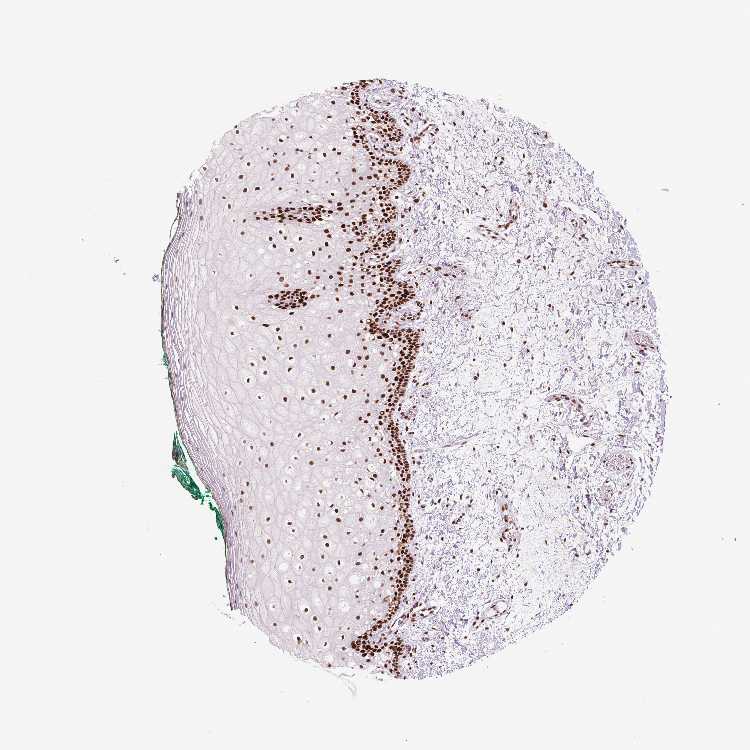

TISSUE PRIMARY DATA ORAL MUCOSA Show tissue menu

Oral mucosa

ORAL MUCOSA - Antibody stainingi

Antibody staining in the annotated cell types in the current human tissue is reported as not detected, low, medium, or high, based on conventional immunohistochemistry profiling in selected tissues. This score is based on the combination of the staining intensity and fraction of stained cells.

Each image is clickable and will lead to virtual microscopy that enables deeper exploration of all samples and also displays staining intensity scores, fraction scores and subcellular localization as well as patient and tissue information for each sample.

Antibody HPA028376Antibody HPA028446Antibody CAB009091Antibody CAB070870

Squamous epithelial cells MediumLowHighHigh